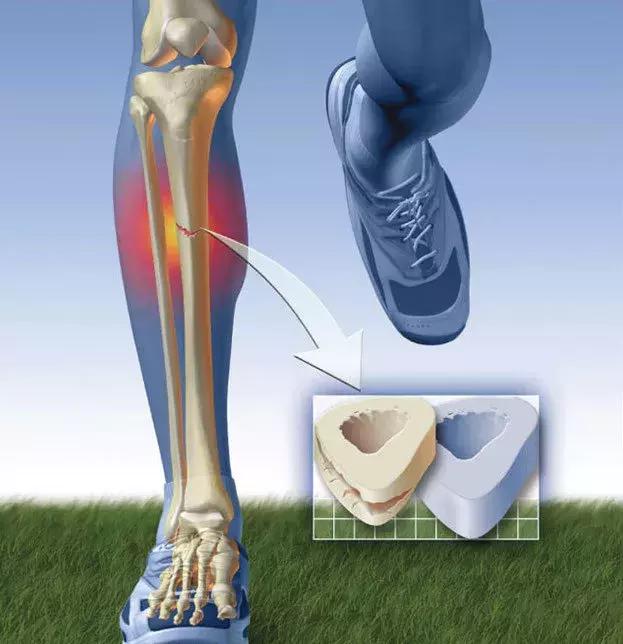

除了急性受伤以外,跑步伤痛中还有一种类型的伤痛也相对比较容易康复,那就是压力性损伤。什么是压力性损伤,顾名思义,不断受到反复作用的冲击性应力作用,从而导致应力集中的现象。跑步是一项非常典型的周期性运动,在一定的时间和距离内,不断完成相同的动作:双脚交替腾空落地。虽然每一次着地时,人体尤其是下肢所受到的冲击力都是有限的,但不断重复的冲击力,就容易引发应力积累和集中,当这种应力积累超过人体承受能力,就会引发疼痛,比如跑者常常发生的小腿疼痛和膝盖疼痛就是这种情况。

小腿疼痛最常见就是胫骨应力综合征,是应力在小腿胫骨不断积累的表现,而在坚硬地面上跑步,加之跑鞋和跑姿问题,就容易导致小腿疼痛。而一些跑者跑步跑多了,出现膝盖疼痛,在初期同样是应力性问题,应力积累导致膝关节内高压,膝关节里的关节软骨本身没有神经,即使受损也不应该引起疼痛,但软骨下方却神经丰富,因此,如果软骨下方持续受压,就会引起疼痛和不适,如果只是关节腔内高压,或者髌骨下端静脉回流受阻所引发的疼痛,都是可逆的,大部分经过休息和治疗后缓解,也不会影响日后的运动。